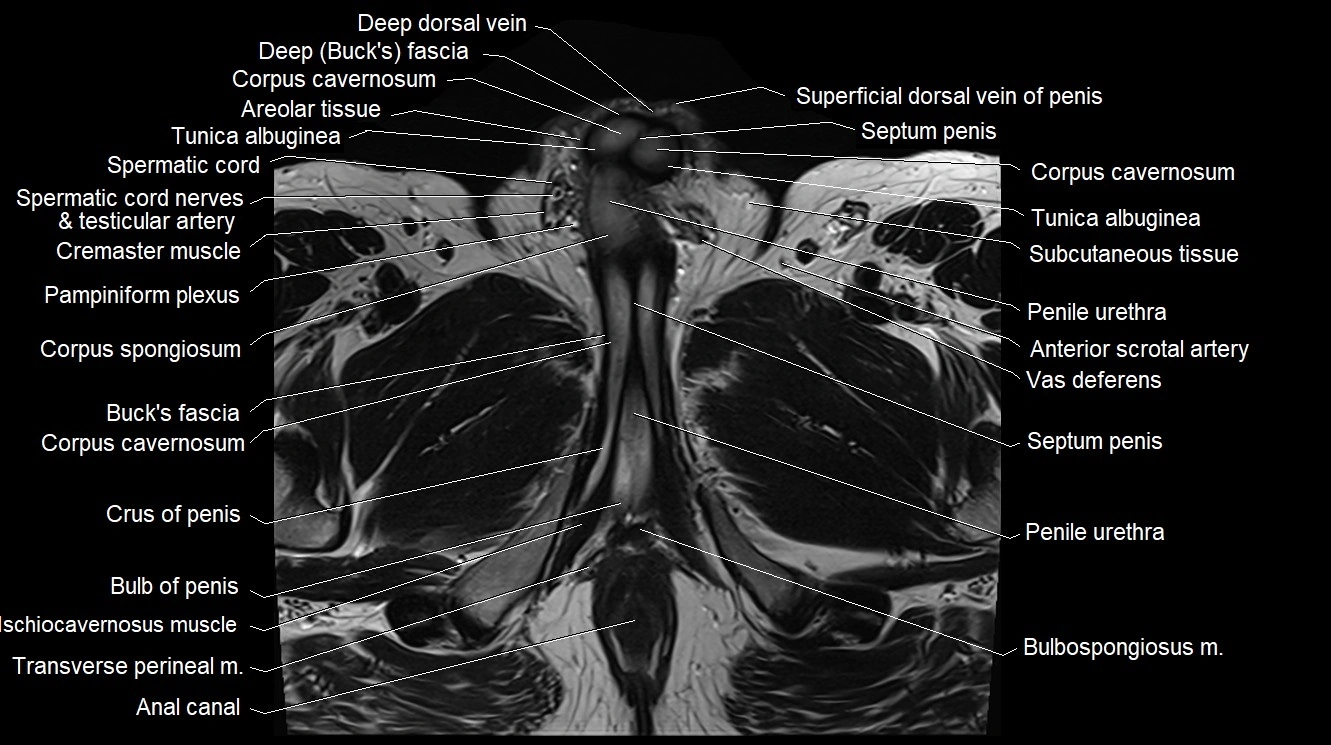

MRI image